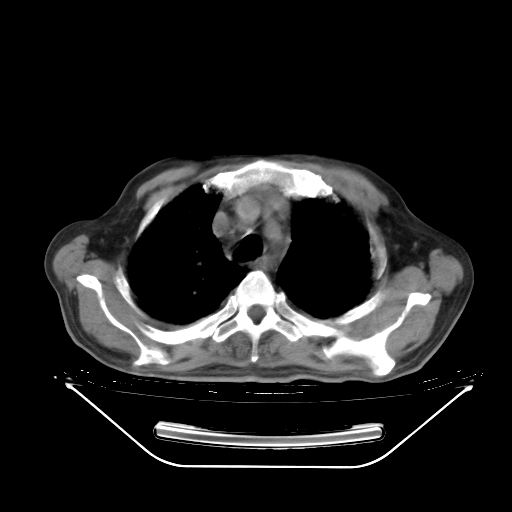

今天复查肺部CT,发现双肺广泛磨玻璃样改变。所以我把3月19日和5月9日相隔50天的肺部CT上传。请大家会诊。

2009年3月19日肺部CT片。

2009年3月19日肺部CT

5月9日肺部CT(在4月27日齐鲁医院肺部CT描述部分肺组织磨玻璃样改变,12天后肺组织广泛磨玻璃样改变)

大致读了系列胸部CT:纵隔窗无明显异常,肺窗:从4、27至今:主要是双肺中下野外带可见毛玻璃样改变,目前处于急性肺泡炎阶段,至于原因考虑1、结替组织或胶原血管性疾病所致?2、恶性疾病如恶组在肺部所致的表现或细支气管肺泡癌?3、药物或其它原因如肺蛋白沉着症所致肺泡炎目前不太可能?总之,明天就去请我院的呼吸科、感染科、血液科和临免专家会诊哈。